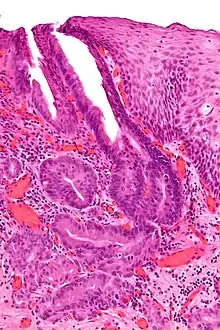

Oesophagogastric junctional adenocarcinoma (OGJ adenocarcinoma) is a cancer of the lower part of the oesophagus with a rising incidence in Western countries.[1] This disease is often linked to Barrett's oesophagus.

The incidence of OGJ adenocarcinoma is rising rapidly in Western countries especially in recent decades, in contrast to the declining frequency of distal gastric adenocarcinoma. Treatment options for adenocarcinomas involving the oesophagogastric junction are limited and the overall prognosis is extremely poor, with a five-year survival rate of approximately 30% with surgery alone.[2]